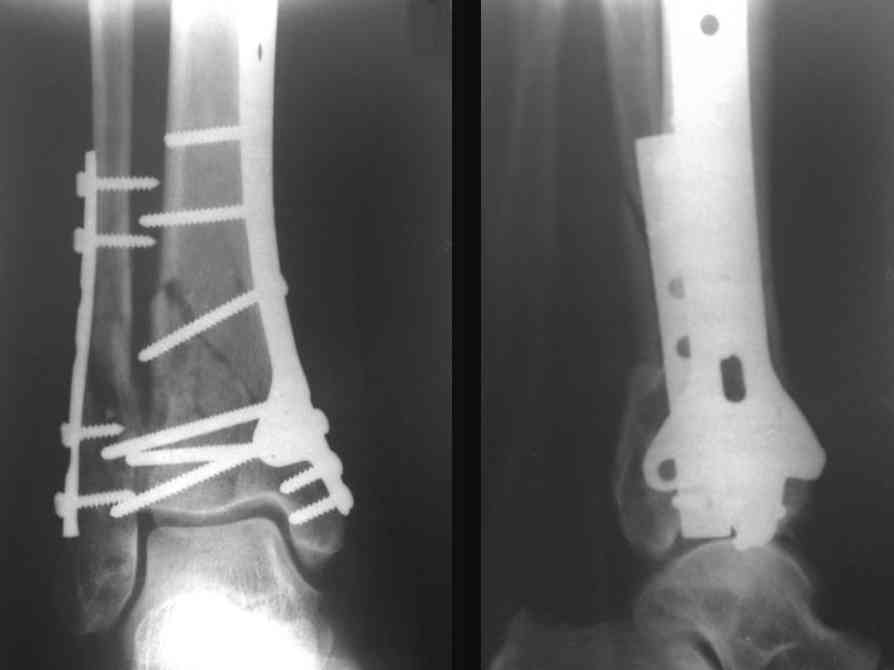

Ja operiroval bolnogo po Vashemu, hotia sam ni ochen' ubezden' v itom, t.k. bolnoi otkazalsa na proch' ot ex.fix, ja emu sdelal ORIF + Kostnia plastika, snimky prelogiottsa,

На рентгенограммах типичный перелом пилона по типу С-3. есть опыт до 100 открытых опреаций у нас в клинике. 20 примерно в год. Принцип один -все внутрисуставные переломы нуждаются в открытой репозиции и внутренней стабильной фиксации. При поступлении КТ не надо, так как получается только нагромождение костей. Истинной картины нет. Главное восстановить длину малоберцовой кости - это ключ к успеху. При поступлении меньше всего надо думать о сосудистых расстройствах, т.к. сама операция и репозиция даже сначала частичная даёт улучшение сосудитых нарушений. Причём очень быстро. Операция в 2этапа. При поступлении доступ позади наружной лодыжки, причём обязательно. После этого репозиция малоберцовой кости и фиксация пластиной 1/3 трубки под винт 3,5. Дренаж и любой аппарат наружной фиксации. Затем после спадения отёка на 5-7-10 день аппрат снимается и дугообразный разрез спереди от медиальной лодыжки 10-12 см. Главной чтобы расстояние между 1 и вторым разрезом было не меньше 7-8 см. Тогда не будет некрозов лоскутов. Таранная кость используется как матрица на неё укладываются отломки и фиксируются пицами. Ренг-контроль. Отломки лежат все отдельно, но ничего не высыпется. При переломах С-3 всегда нужна костная пластика (из крыла). Фиксация пластиной лист клевера простой или LCP. Гипс не нужен. Дренаж до 48 часов. Операция длится 3-4 часа обязательно без жгута. Посылаю примерно такой же случай.

Кстати, при переломах переднего края по классификации АО В-3 при переломах пилона пластина укладывается по передней поверхности. Она достаточно тонкая и эластичная, не надо этого бояться. Посылаю три снимка.